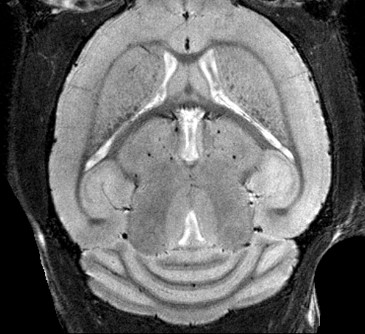

• Crisp and highly resolved images with a gradient strength of up to 760 mT/m

• Complete RF coil portfolio for mice and rats available, including coils for head, brain, cardiac, spine, body, multi-channel array coils with up to 8 channels, and x-nuclei

• Over 100 validated and ready to use in vivo protocols and scan programs for mice and rats